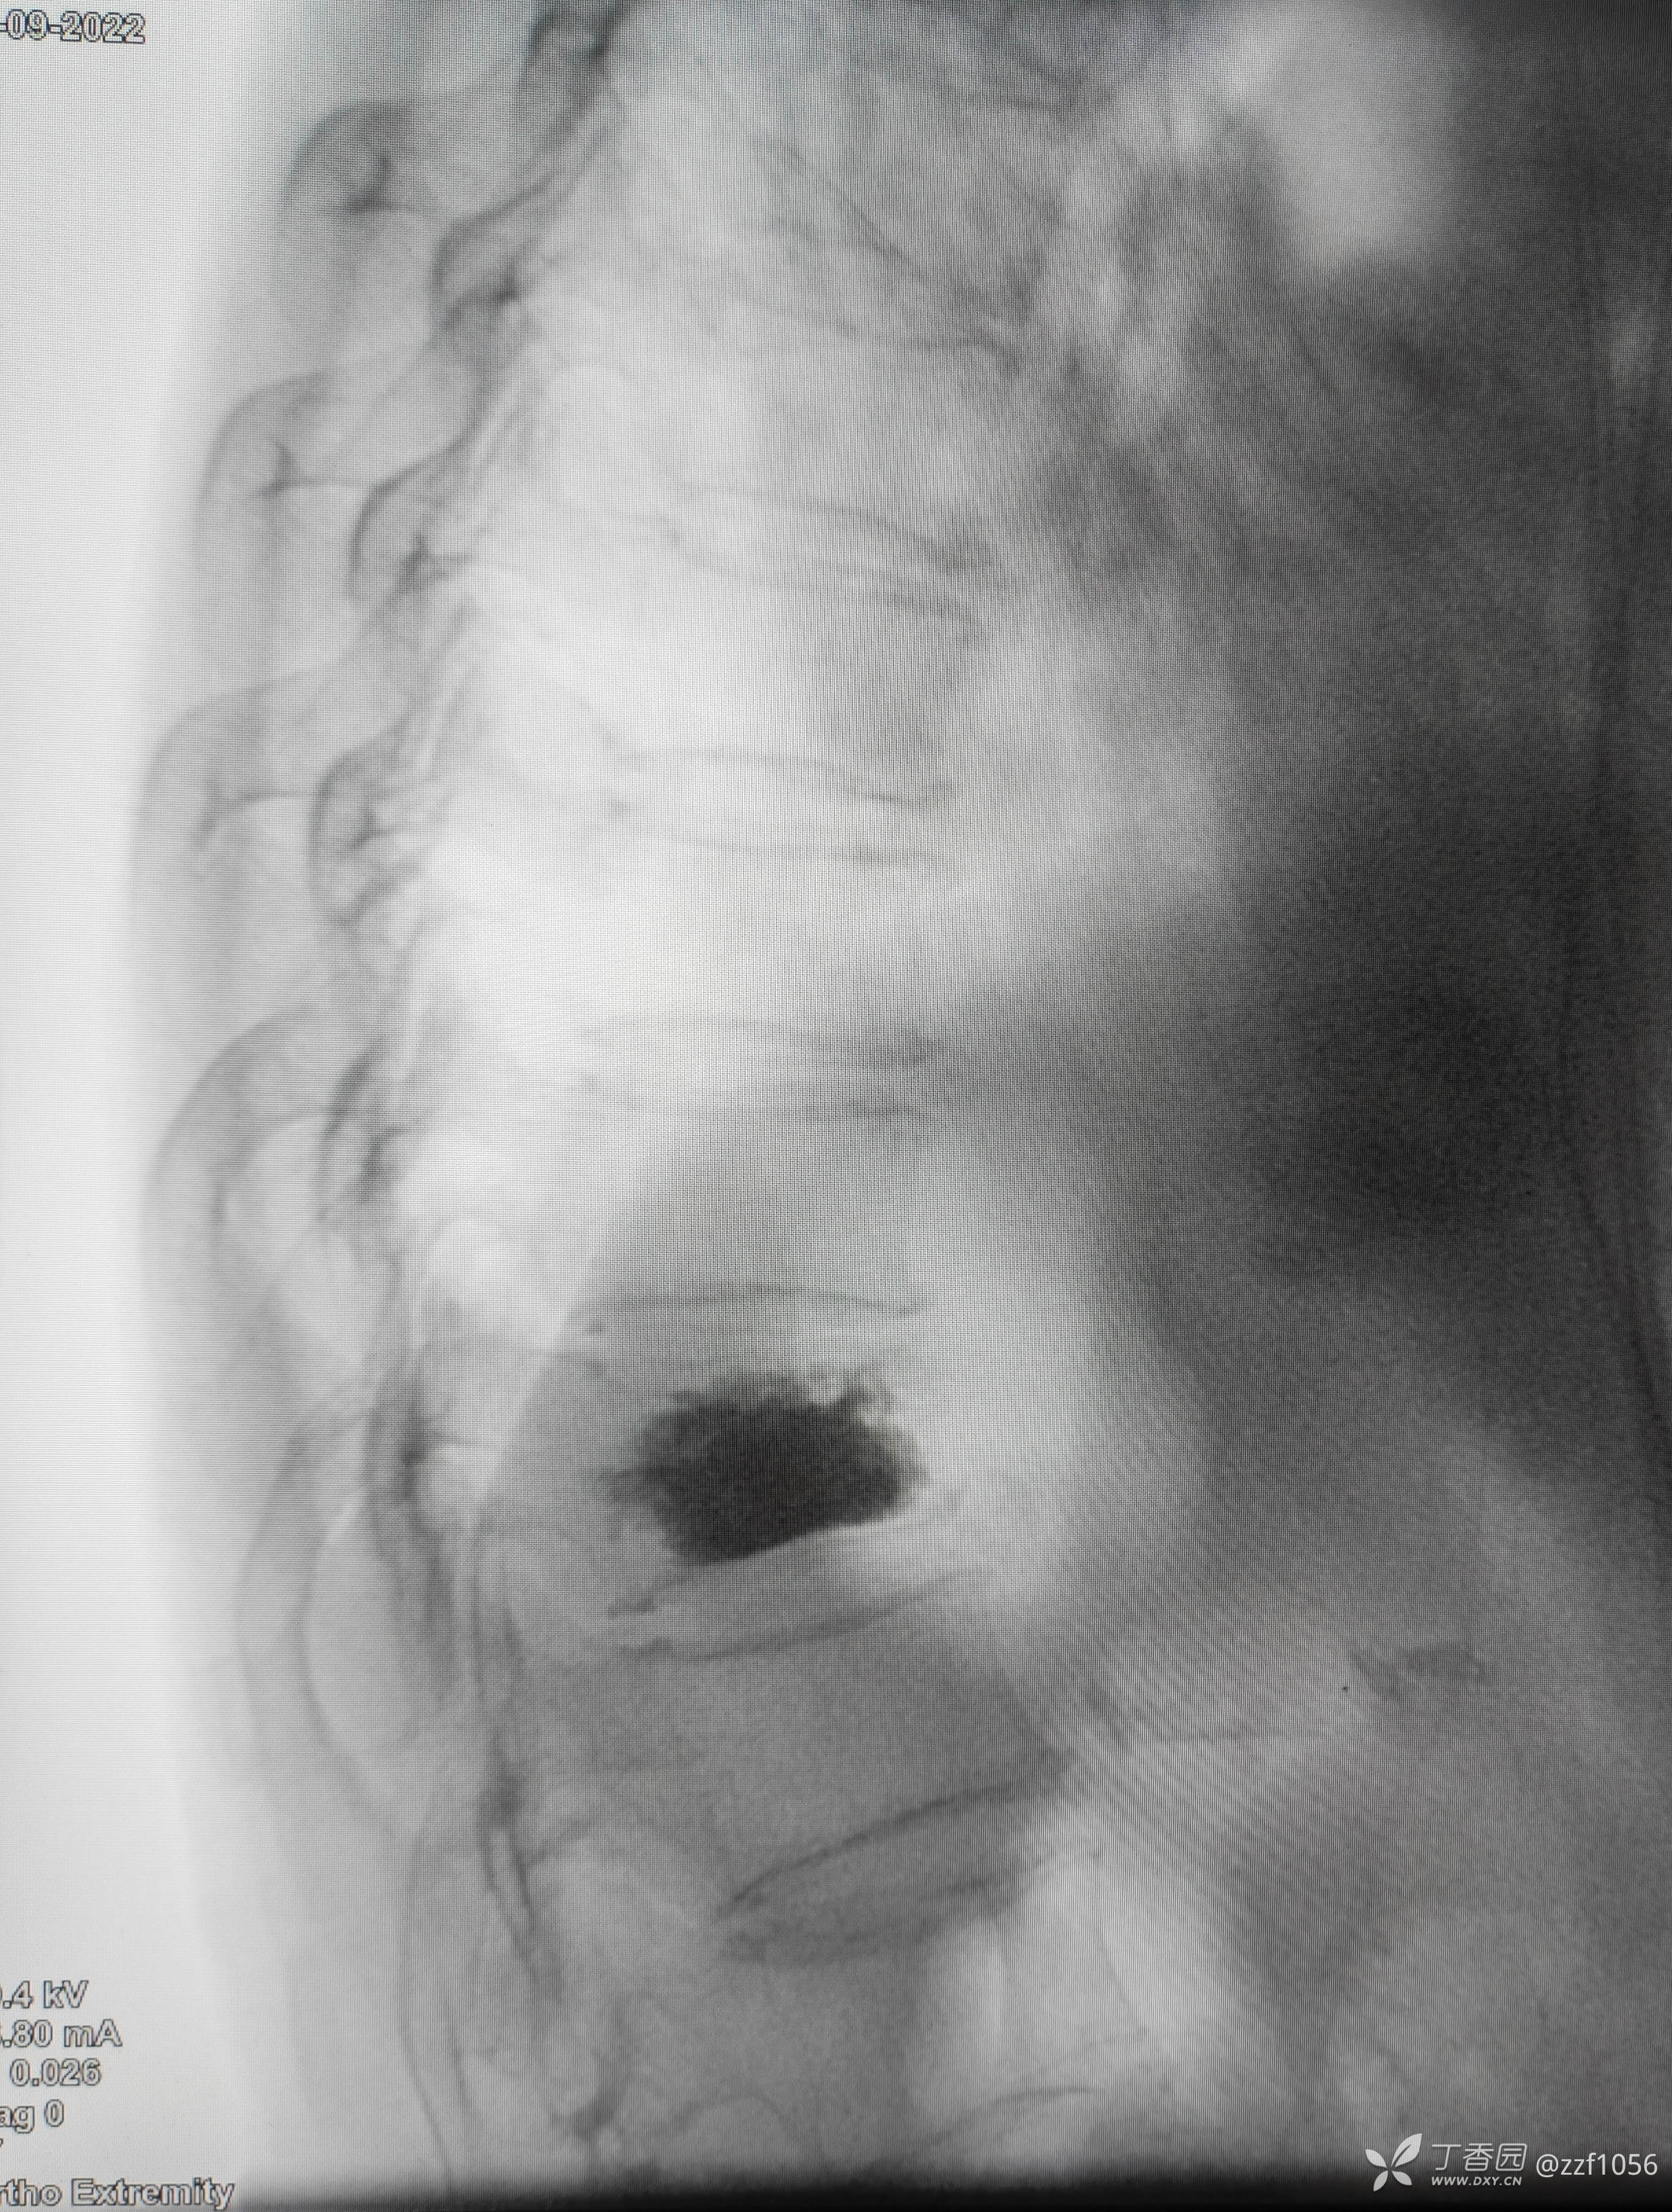

那么看术后CT

可是患者仍感觉腰痛,两个月后去B医院就诊,B医院观点是对侧再次穿刺加注骨水泥,站友们你的观点呢?

据病人描述加注后疼痛缓解

术后

实打实给同行留了余地,更希望同行不相轻吧!